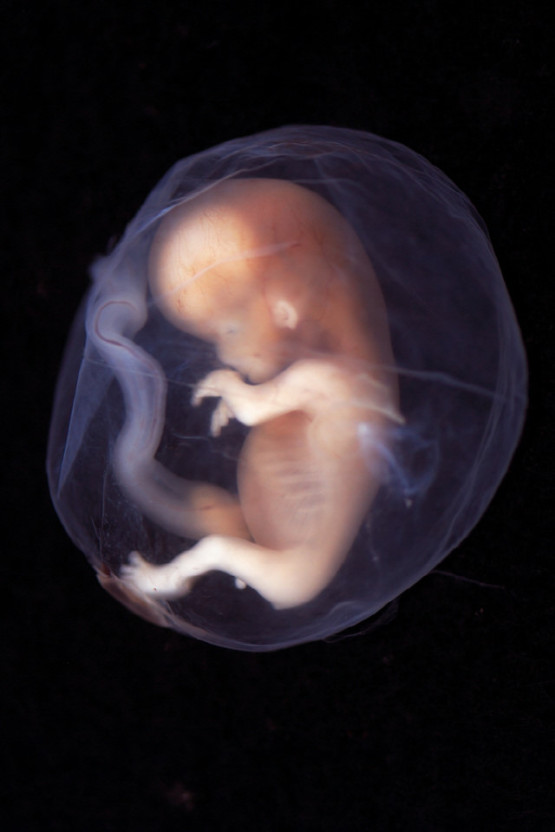

현재 의료법 제20조 2항은 임신 32주 이전에 의료인이 태아의 성별을 알려줄 수 없도록 규정하고 있었습니다. 이는 남아 선호 사상에 기인한 여아 낙태 예방을 위한 조항으로 설계되었습니다.

최근에는 낮은 출산율과 남아 선호 사상의 변화로 인해 부모의 태아 성별 정보 접근 권리에 대한 주장이 높아지고 있습니다.